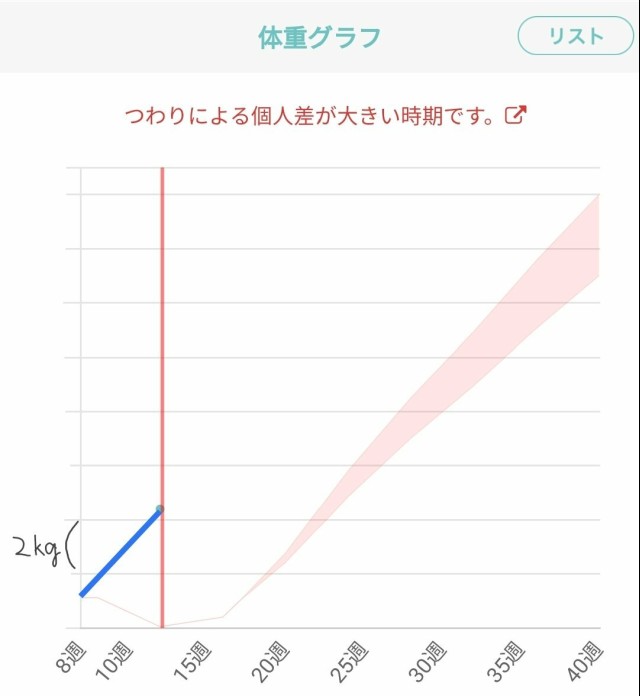

体重管理 スタートダッシュ早すぎワロタ?妊娠後期は息をするだけで体重が増えるのに(絶望)

体重管理 今日から24週目 妊娠6ヶ月が終わって、妊娠前よりも体重は+3kgくらい 名前の候補も2つまで絞った(*´-`)? 24週までに里帰り先の病院受診しないといけないと分かった時は 大分先の話に感じてたんだけどあっという間? 0d